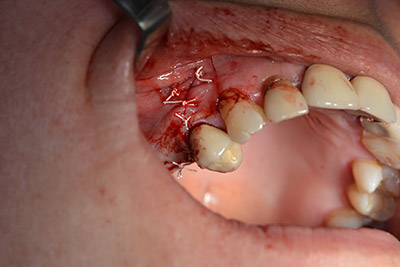

Per ridurre l'accrescimento nella regione 14, con il consenso della paziente si opta per il posizionamento e l'inclinazione dell'impianto 16 in direzione dorso-craniale (fig. 8).

Immagine 8: DVT con piano dell'angolo di inserimento per impianto 16